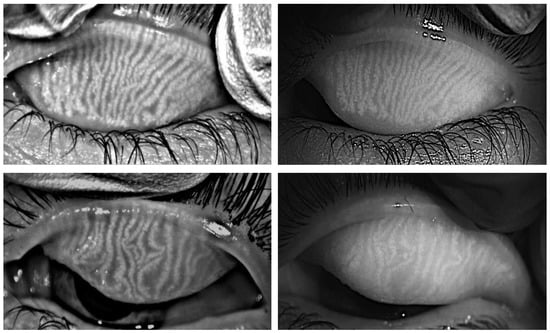

3.5. MG Images Captured with the Two Instruments